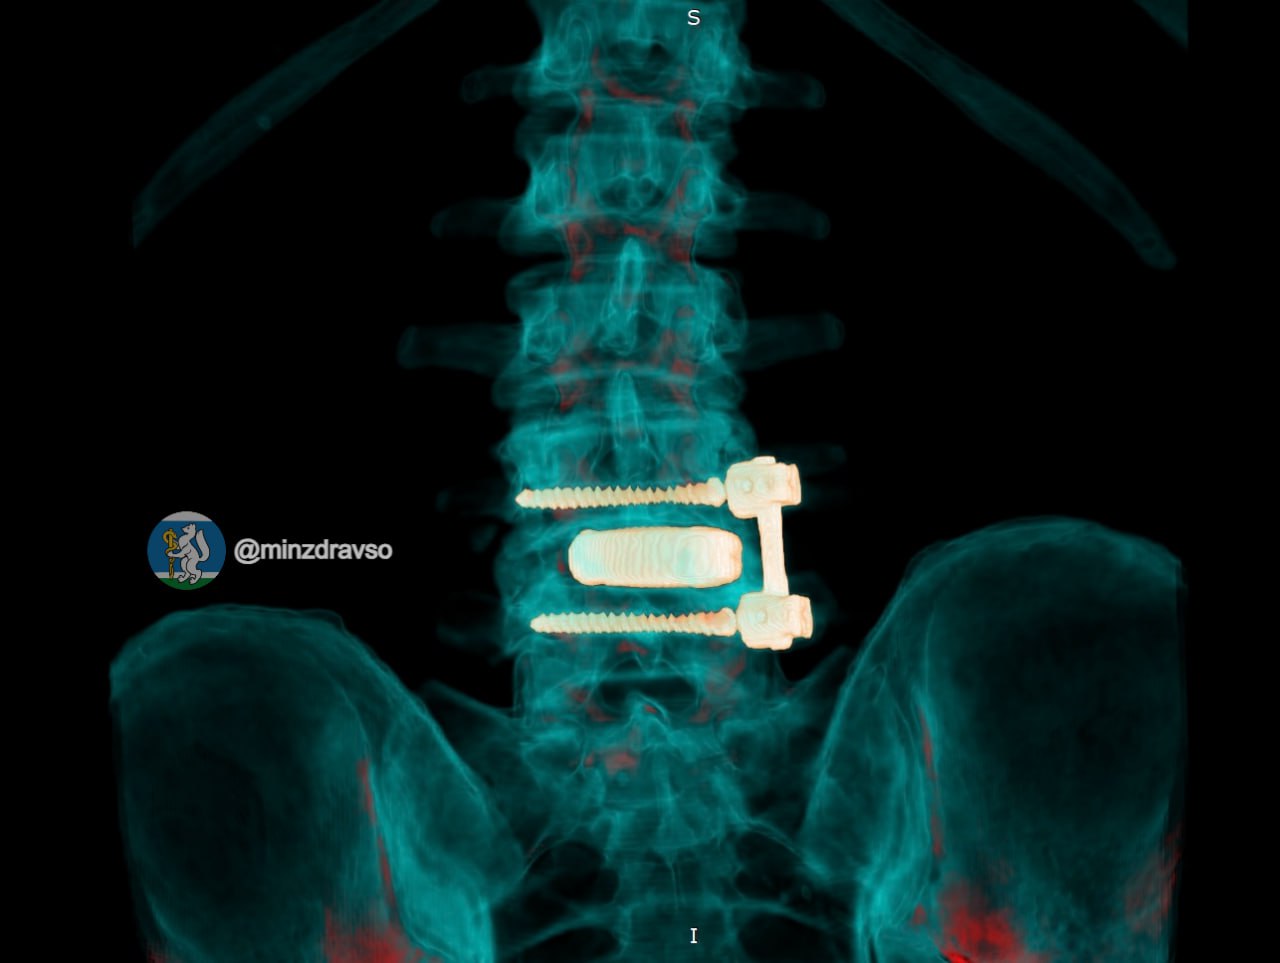

Чтобы помочь пациенту, в госпитале для ветеранов войн была разработана поэтапная тактика. На первом этапе хирурги удалили инфицированную конструкцию и провели санацию очага воспаления. После курса антибактериальной терапии и подготовки наступил ключевой этап — восстановление опороспособности позвоночника.

«В таких случаях недостаточно просто убрать инфекцию. Необходимо восстановить стабильность позвоночника, чтобы человек мог жить активно. Мы применили комбинированную реконструкцию с использованием современных технологий», — пояснил оперирующий нейрохирург госпиталя Иван Доценко.

Пациенту установили титановый 3D-имплант, изготовленный по индивидуальным параметрам. Фиксацию выполнили российскими спонгиозными винтами. Уже в первые сутки после операции болевой синдром полностью купировался, пациент самостоятельно встал и начал ходить.